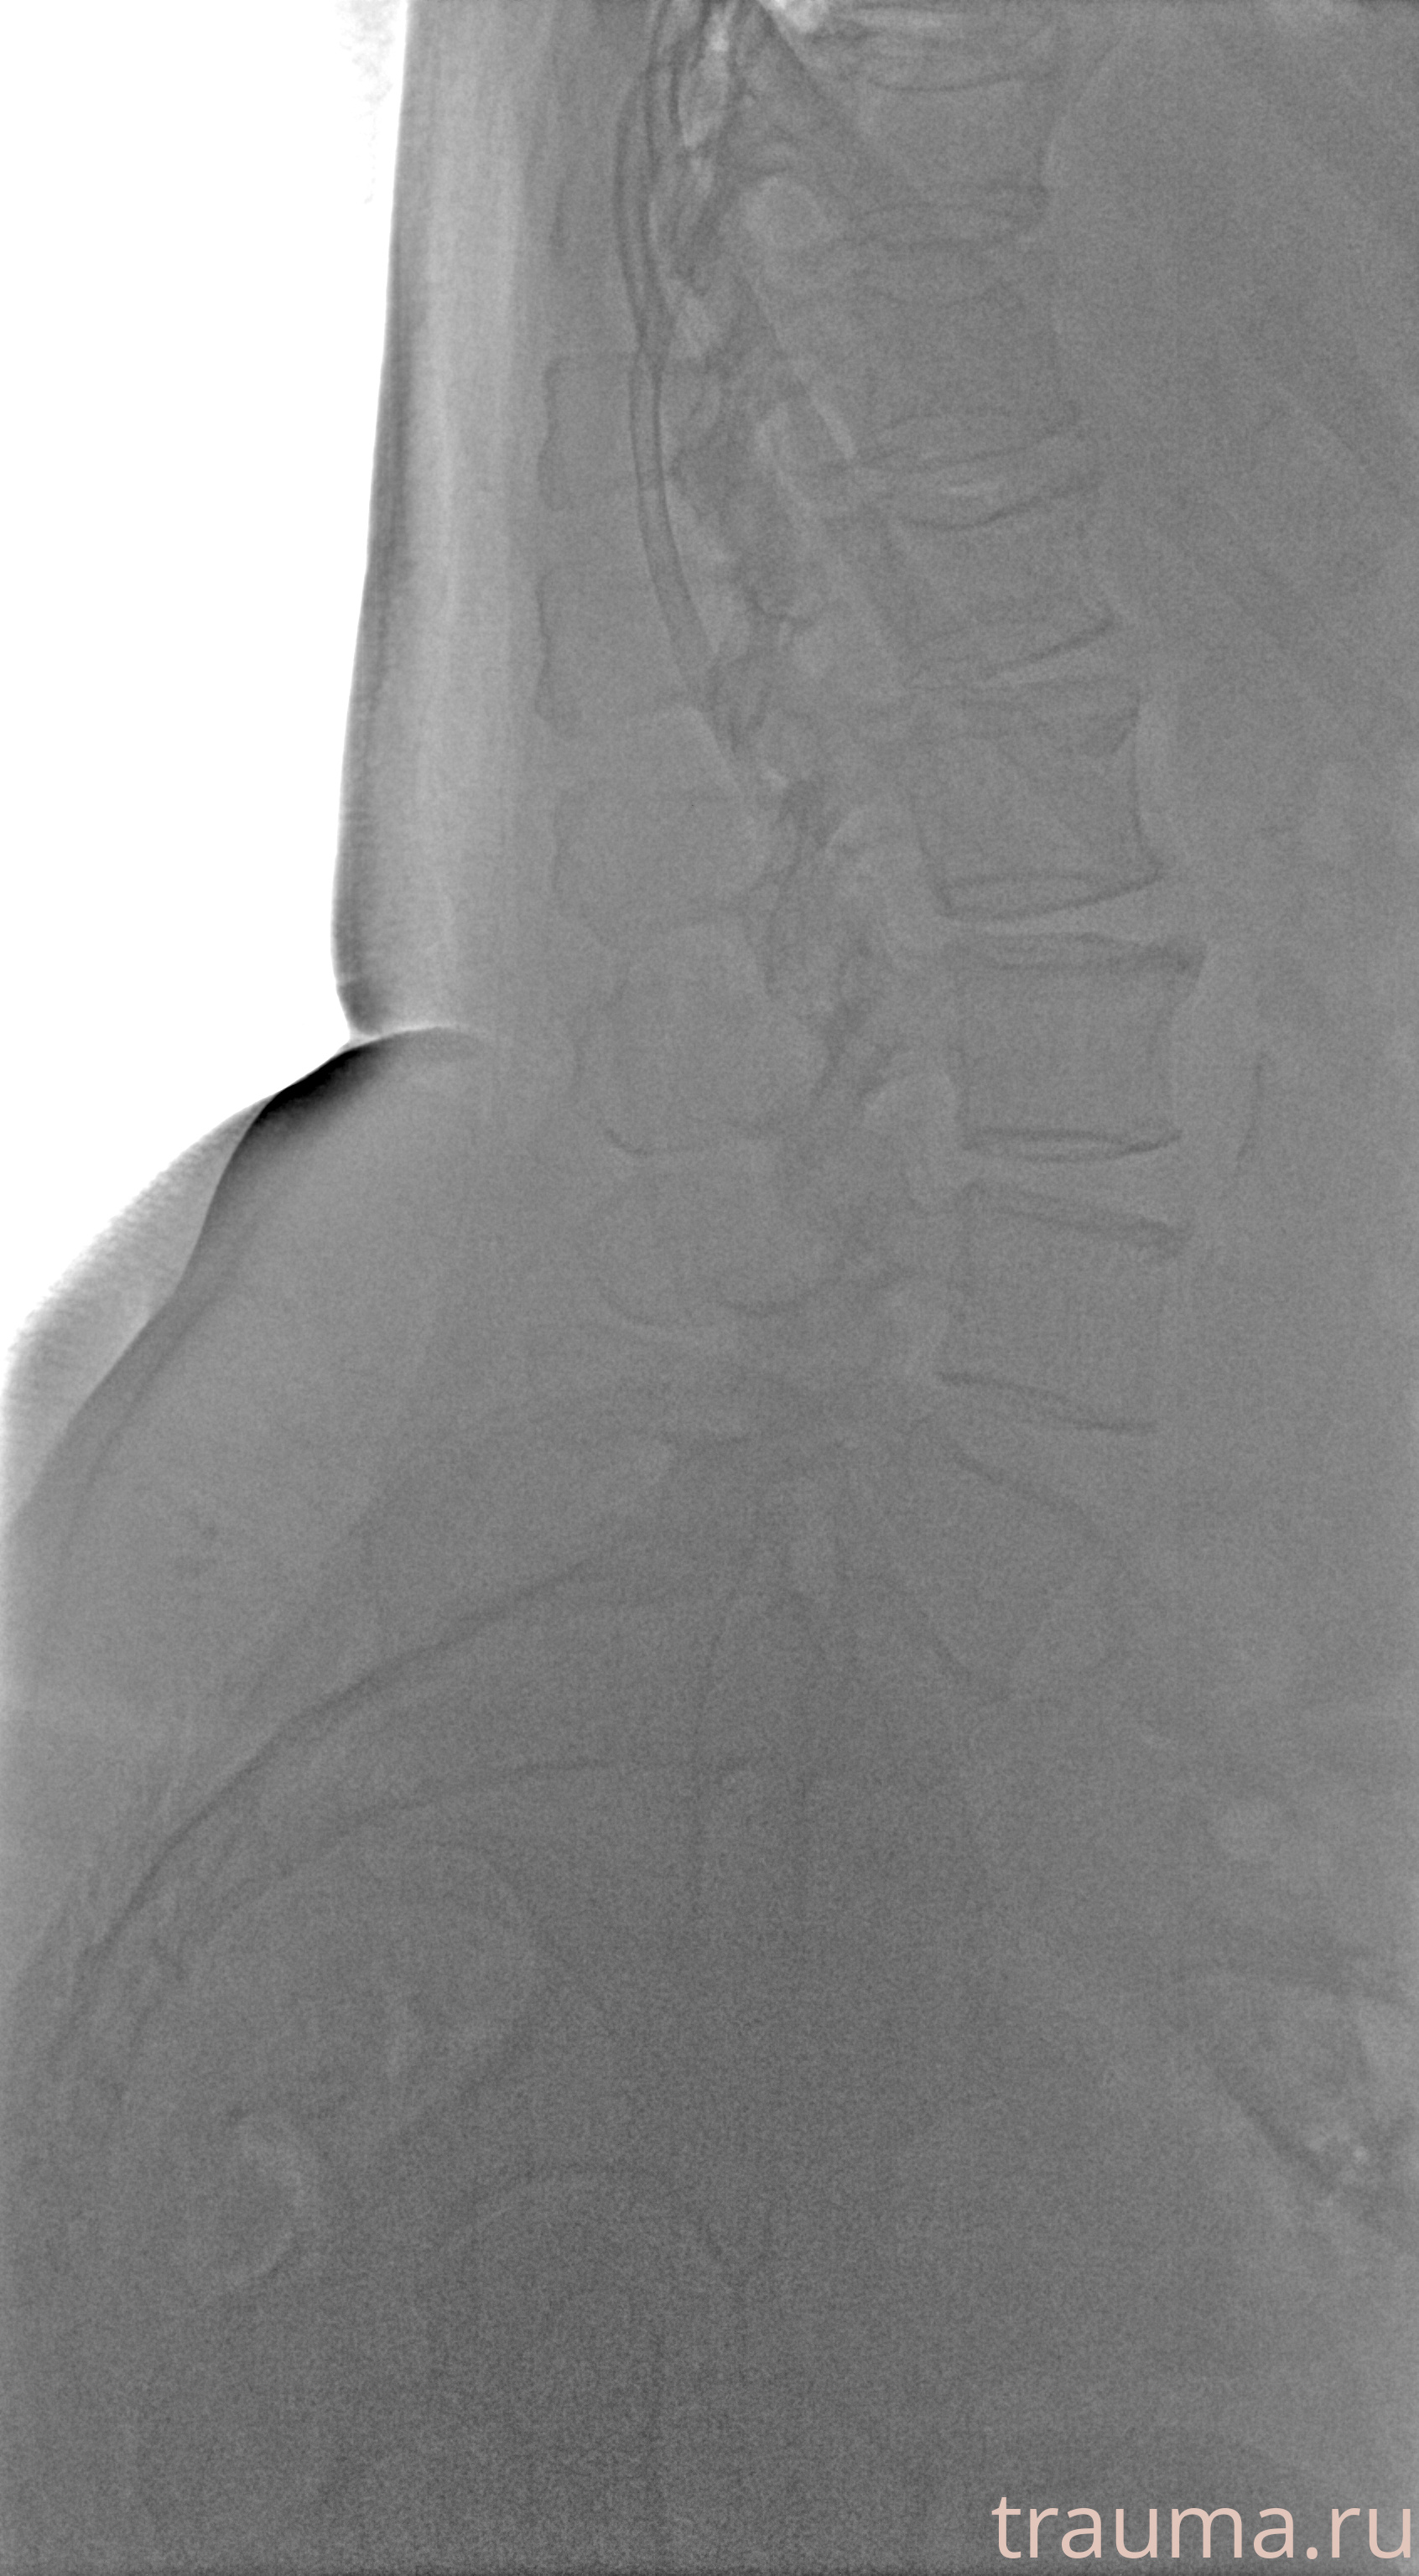

Рентгенограммы

Рентген на дому: по вашему адресу приезжает врач-рентгенолог, травматолог-ортопед с мобильным рентгеновским аппаратом, проводит диагностику травмы или заболевания, делает необходимые рентгенограммы, дает рекомендации по дальнейшему лечению. Получить качественные снимки в домашних условиях возможно благодаря уникальной методике, разработанной МосРентген Центром для института  Склифосовского